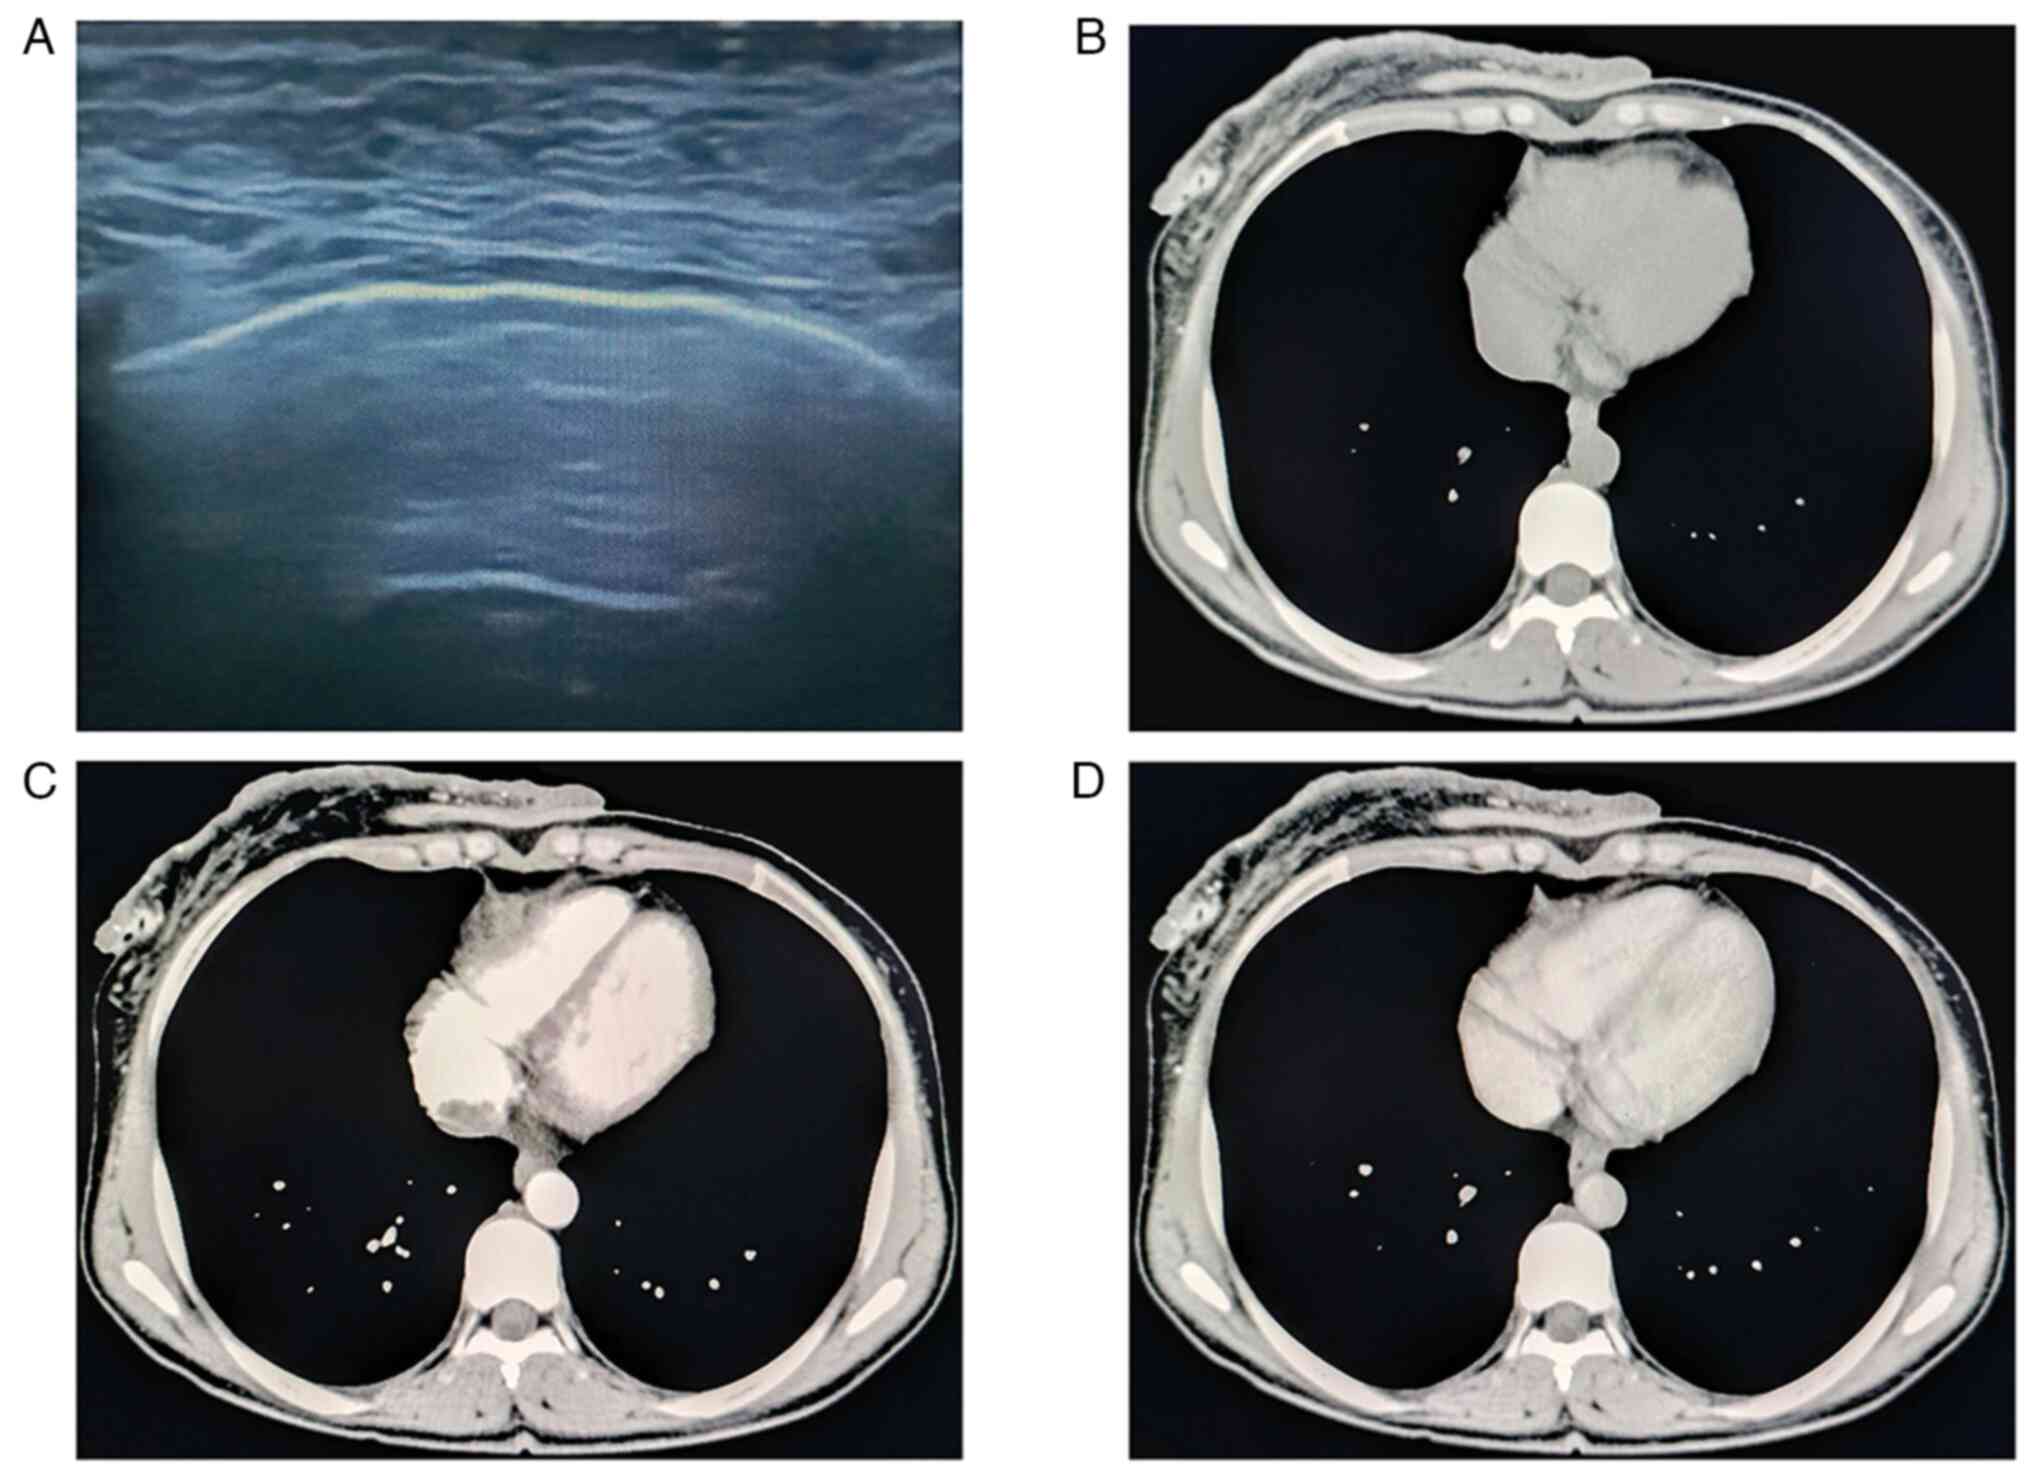

Typical presentation of neurofibromatosis type I in a patient with giant cutaneous neoplasm and café au lait spots: A case report

Neurofibromatosis type 1 (NF1), which is also known as von Recklinghausen's disease, is a multisystem genetic disease that is principally associated with cutaneous, neurologic and orthopedic manifestations. The present case report described an unusual case with a giant cutaneous neoplasm on the right breast skin of a 36‑year‑old female who was admitted to the Department of Breast Surgery at the Affiliated Tumor Hospital of Xinjiang Medical University (Urumqi, China). Skin mass excision was performed and histopathology confirmed the diagnosis of thoracic plexiform neurofibroma as a primary presentation of NF1. The clinical implementation of NF1 therapies necessitates meticulous consideration of various factors and should involve a multidisciplinary team with expertise in NF1.